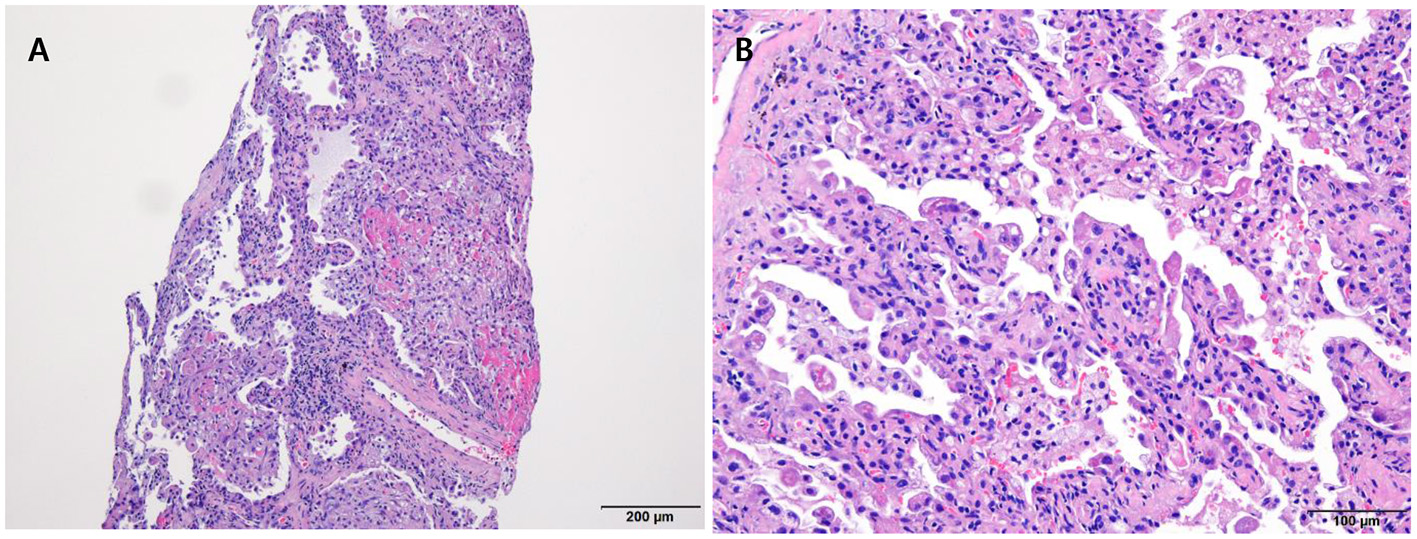

The laboratory workup showed that the level of the total bilirubin was 0.71 mg/dL (reference range, 0.22–1.3), the aspartate aminotransferase level was 358 U/L (reference range, 10–37), the alanine aminotransferase level was 177 U/L (reference range, 10–37), and the prothrombin time was 1.90 International Normalized Ratio (INR) (reference range, 0.8–1.2). Enhanced computed tomography (CT) showed diffusely increased liver intensity and scattered hyper attenuated nodular consolidations in the subpleural areas of both lungs (Figures 1A,B). To evaluate the possibility of malignancy, positron emission tomography–CT (PET–CT) was performed, and multiple hypermetabolic lesions (maximal standardized uptake values 7.3, Figure 1C) were examined. To confirm the diagnosis of the lung lesions, transthoracic needle biopsy was performed, and the pathologic examination showed fibrinoid interstitial inflammation with atypical change of type II pneumocytes and intra-alveolar foamy macrophages (Figure 2). Using both the CT and biopsy findings, we could diagnose the amiodarone-induced hepatic and pulmonary toxicity.

Figure 2

Pathologic examination of the lung via trans-thoracic needle biopsy showing amiodarone-induced lung toxicity. (A) Chronic interstitial pneumonitis and interstitial fibrosis and focal fibrinoid necrosis. (B) Accumulation of foamy macrophages within alveolar spaces.